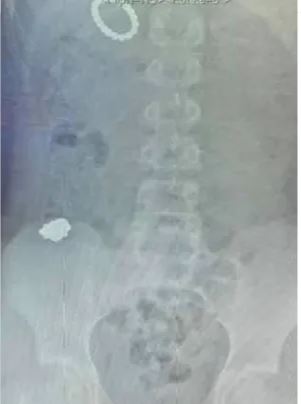

Un menor de 12 años tuvo que ser operado de emergencia tras tragarse 54 imanes como un “experimento”.

El menor tuvo que ser intervenido de urgencia y los médicos pudieron extraerle exitosamente los 54 imanes que se tragó, y tuvo que permanecer en cama para recuperarse, así mismo, se señaló que duró 10 días vomitando un líquido verde causado por una fuga intestinal, lo que lo llevó a ser alimentado por sonda.